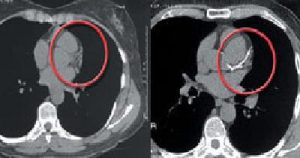

Why EBT?

The only heart test you need

Mammogram of the Heart